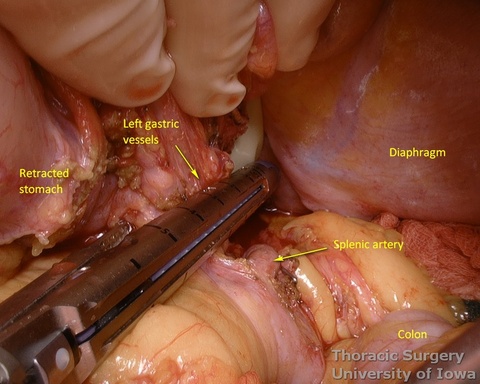

- Peritoneum is incised, protecting the splenic artery and pancreas. 1-2 mm posterior gastric artery, originating from the proximal splenic artery fs present (in half of individuals) and is divided.

- Once the stomach is mobilized and reflected anteriorly, the left gastric vascular pedicle is identified and dissected close to the origin for adequate lymphadenectomy. Care is taken to not injure splenic artery and pancreas.

- Left gastric vessels are divided with an endoscopic linear cutting stapler proximally, including all adjacent lymph nodes in the specimen.